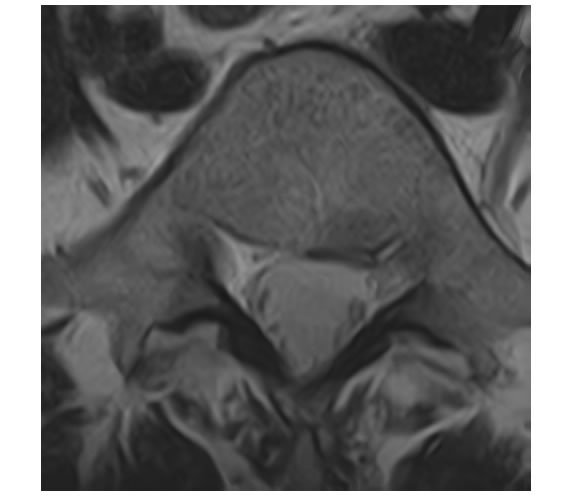

| 腰部脊柱管狭窄症 | |

|---|---|

| 椎間板以外に、靭帯や骨によって神経が圧迫されている状態となります。50歳以上に多いです。 | ![]() (腰椎を輪切りにした図) |